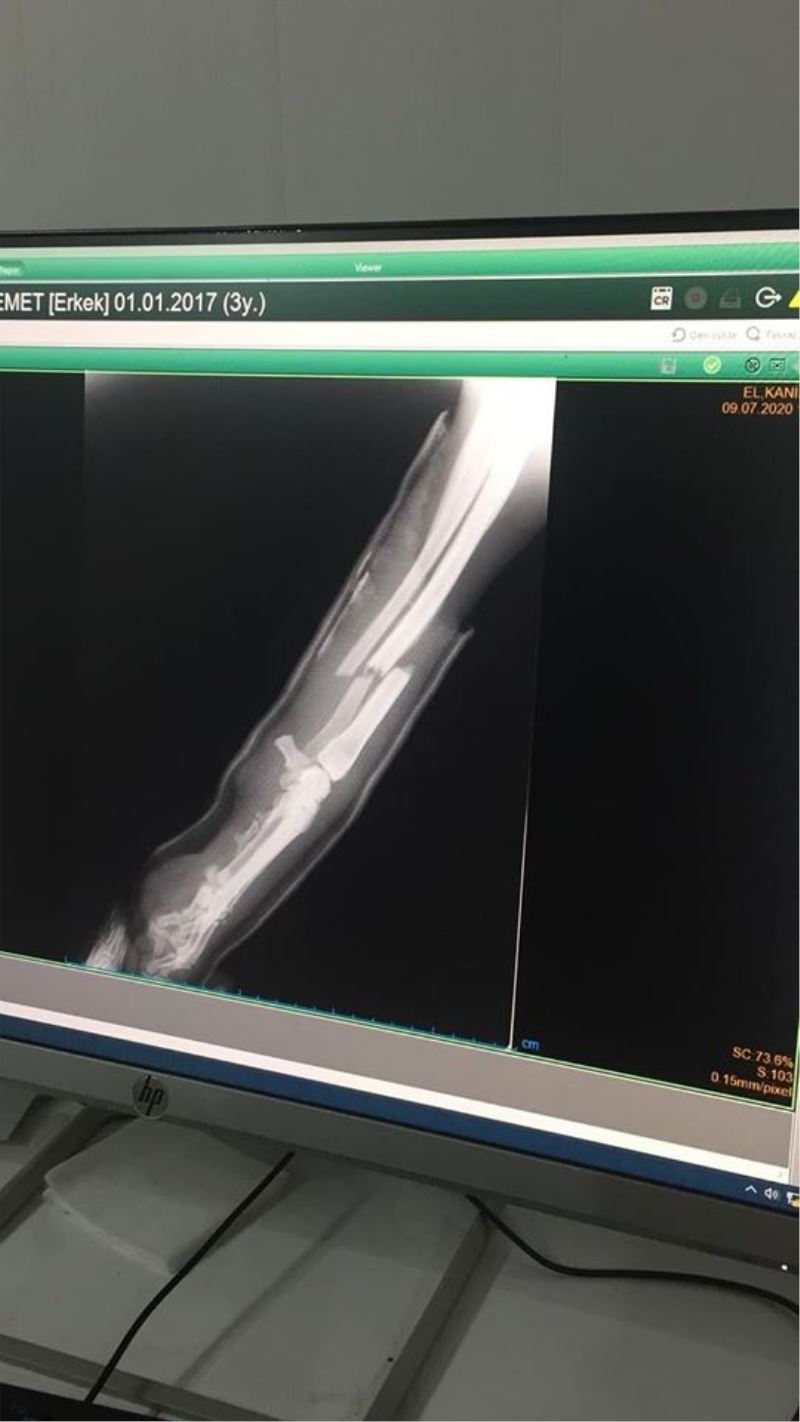

Kütahya’nın Emet ilçesinde trafik kazasında yaralanan köpeğin ayağına ameliyatla platin takıldı.

Emet Belediyesi Zabıta Amirliği ekipleri, bir arabanın çarpması sonucu ayağından yaralanan sokak köpeğini veterinerin ilk müdahalesinin ardından Tavşanlı ilçesindeki kliniğe götürdü. Ekiplere burada yapılan incelemede köpeğin ameliyat olması gerektiği belirtildi. Tavşanlı Yıldız Veterinerlik Hekimi Hayrettin Yıldız tarafından başarılı bir ameliyat ile köpeğin kırılan sağ bacağına platin takıldı.

Sokak hayvanlarının bakım ve tedavileri için amirliklerince gerekli çalışmaların yürütüldüğünü ifade eden Emet Belediyesi Zabıta Amiri Metin Şenel, ”Belediye Başkanımız Hüseyin Doğan’ın talimatları doğrultusunda sokak hayvanlarımız için yoğun bir çalışma içerisindeyiz. Ameliyat edilen köpeğimiz trafik kazasında ayağından yaralanmıştı. İlçemizdeki veterinerlerimizde köpeğin ilk muayenesinin yapılmasının ardından Tavşanlı ilçemizde özel bir veteriner kliniğinde filmlerini çektirdik. Yapılan muayene ve çekilen filmler sonucu Veteriner Hekim Hayrettin Yıldız platin takılması gerektiğini ifade etti. Bizler de sokak hayvanımızı ameliyat ettirerek platini taktırdık. Tedavi süreci devam eden köpeğimiz, iyileştikten sonra doğal ortamına geri bırakılacak" dedi.